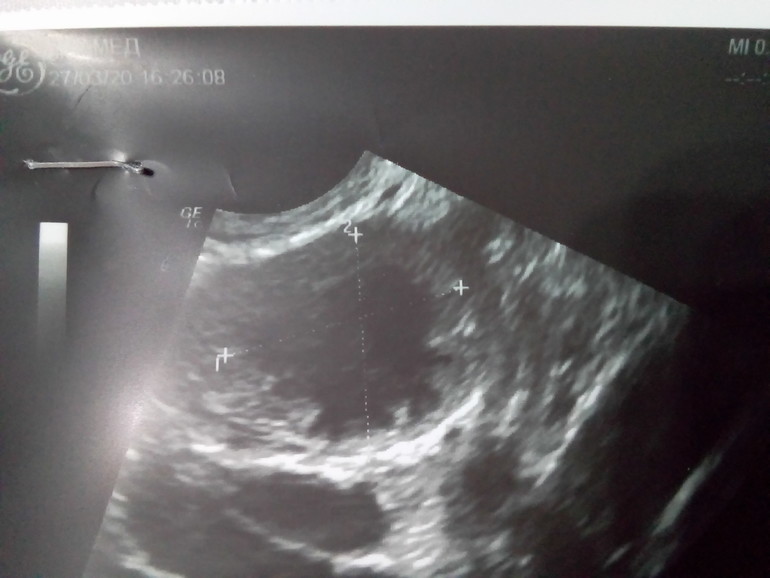

Ниже это ДФ 23*19 мм

Ниже ЖТ 17 мм